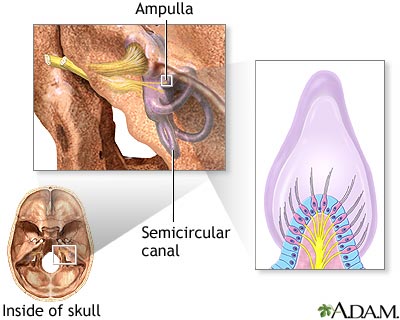

Vertigo is a feeling that you are spinning or moving, or that the world is spinning around you. Vertigo-associated disorders is a related topic.

Vertigo may be due to:

- Benign positional vertigo, a spinning feeling that occurs when you move your head

- Labyrinthitis, a viral infection of the inner ear that usually follows a cold or flu

- Meniere disease, a common inner ear problem that often also causes hearing loss or ringing in the ears (tinnitus)

Surgery may be needed if you have Meniere disease.